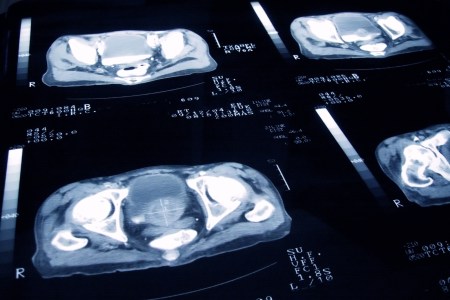

Prostate cancer is a serious matter; advanced prostate cancer, when the cancer has begun to spread through the body, is even more alarming. While early treatment of prostate cancer is often effective, treating it at a more advanced stage is — for understandable reasons — much more challenging. All of which makes the news that doctors have seen evidence that a new treatment could make inroads against more aggressive forms of prostate cancer that much more promising.